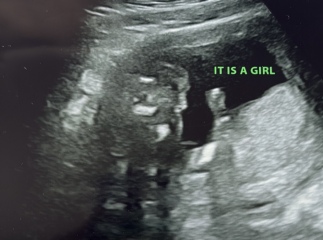

me and my partner recently had our 16 week gender scan. we were told the baby is a girl but i’m slightly paranoid!

baby was in awkward positions and the ultrasound tech told us she was getting different angles to get a definite answer for us!

i’ve attached our scan, would you say this is right for a girl?

gender scan